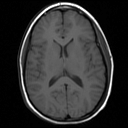

Check out the size of my insula!